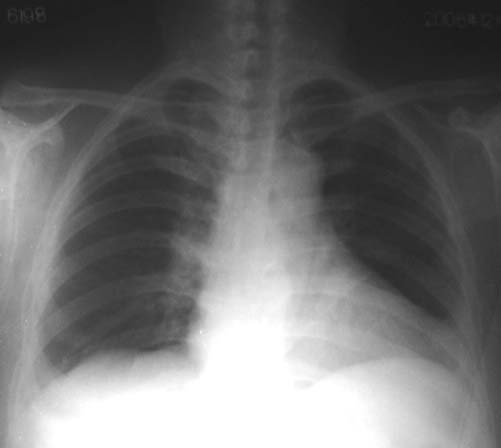

患者,女,63岁,胸闷,气促月余。请看左下肺是正常吗?还是心脏影还是胸膜反应?

只有正位患者横位心,再看也是猜.不过隐约可见肋膈角,应该没问题,是心包脂肪重叠的吧.最好透视转一下,就放心了.

病人是不是较肥,心脏呈横位,可在透视下观察看是否有异常。

赞同3楼的看法。肋膈角隐约可见,应当不是胸膜的病变。考虑为横位心及心包脂肪垫所致。

谢谢各位同行的指导!该病人是较胖的一个人,我用12x15胶片照的时候增感屏都是横起放的,要不是都照不起,当时我也考虑是心脏的重影,现在有各位的看法,也证实的我的这一点,因为停电,所以病人一照好以后便走了,所以没有照侧位,也没有机会透视看了。这一张片子我都是点着烟边抽边照边洗的。所以不怎么好看,呵呵!

考虑为横位心及心包脂肪垫所致

考虑:横位心+心包脂肪垫,透视旋转观察一下就准确。